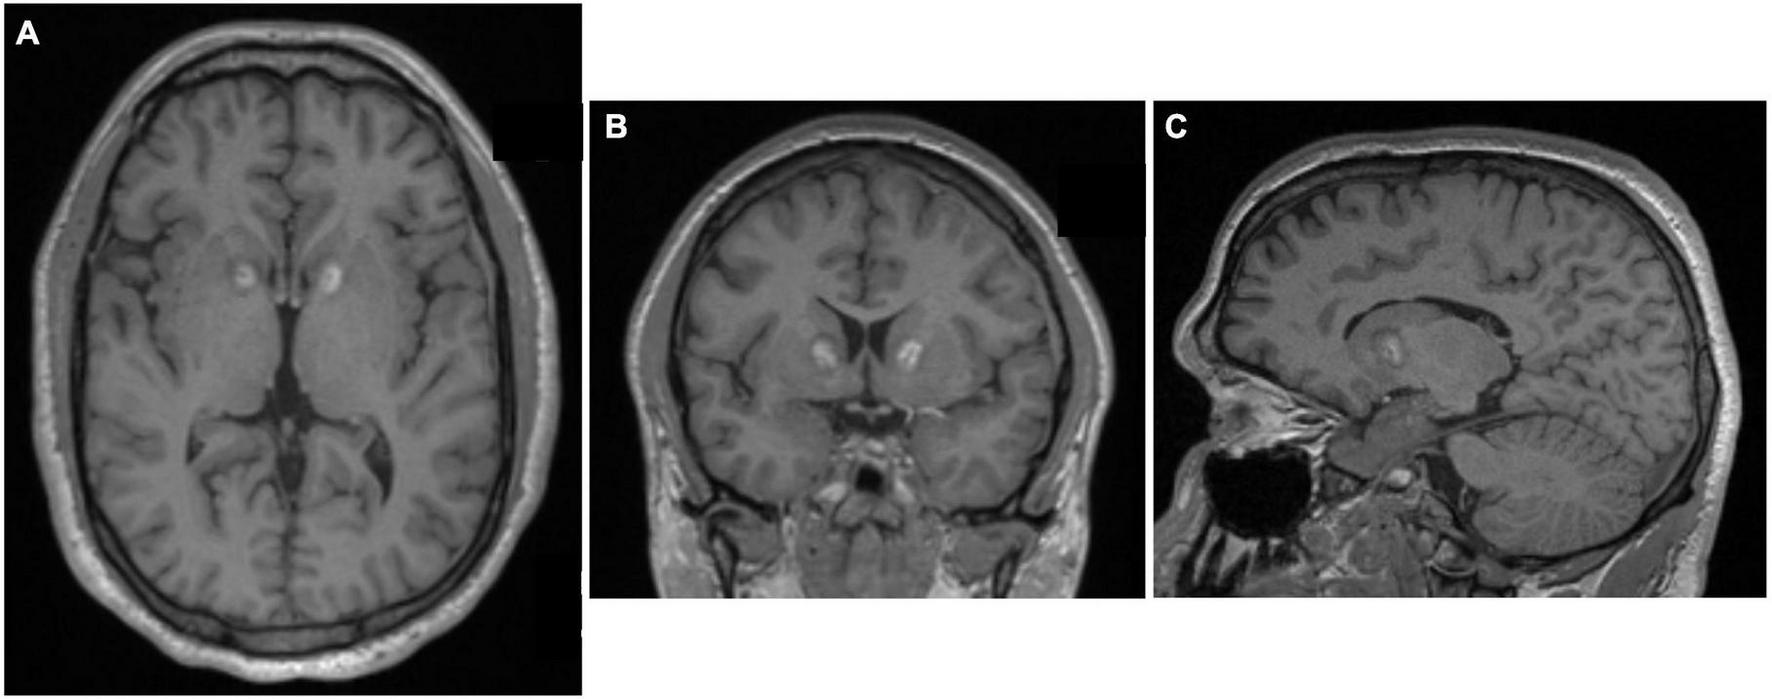

The delayed development of brain cysts after radiosurgical capsulotomy prompted the Brown group to employ an alternative lesioning approach: MRI-guided laser interstitial thermal therapy (LITT) (McLaughlin et al., 2021). In the largest series of LITT for the treatment of psychiatric disease to date, 77.8% of ten patients with severe, intractable OCD who underwent MR-guided LITT capsulotomy were full responders, with full response defined as at least a 35% reduction in YBOCS scores (McLaughlin et al., 2021). The procedure was generally well tolerated, and it appears to have a comparable efficacy to radiosurgical capsulotomy (McLaughlin et al., 2021). Overall responses to LITT are comparable to SRS, but interval to symptom response was much shorter are LITT (Figure 10).

FIGURE 10

Laser interstitial thermal therapy (LITT) capsulotomy for OCD. (A) Axial, (B) Coronal, and (C) Sagittal MPRAGE MRI images after MR-guided LITT. Original figures kindly provided by Dr. Wael F. Asaad, Brown University.